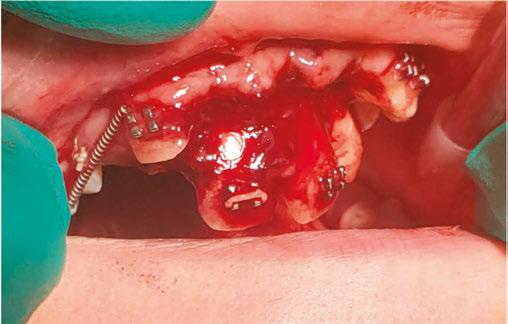

Luckily, the young boy was undergoing orthodontic treatment so the avulsed teeth remained in the oral cavity. As you can see from the clinical photograph in Figure 1, teeth Nos. 8, 9, and 10 would not have remained in the mouth if the orthodontic wire was not in place.

Two days after treatment, the patient was seen in my practice after the teeth were splinted back in place by the orthodontist. Figures 2A-2B are the preoperative radiographs after the teeth were reimplanted.

One can already appreciate the inflammatory resorption that is occurring at the apices of teeth Nos. 9 and 10. These images were taken just two days after the trauma.

My goal at the first visit was to understand the trauma with respect to the extraoral dry time of the teeth (how long were

the teeth outside of the mouth), get a full picture of the type of trauma that occurred, and to make sure that the teeth were stabilized.

Endodontic treatment began a few days after my initial examination. We did not want to start treatment right away, but we also didn’t want to wait too long to start treatment — we needed to give the periodontal ligament a moment to restabilize prior to treatment so we didn’t get further unwanted consequences down the road. But if we waited too long, inflammatory resorption would start to set in, and we would start to lose tooth structure. Endodontic treatment should be started within 7–10 days after the trauma to avoid these two potential consequences.